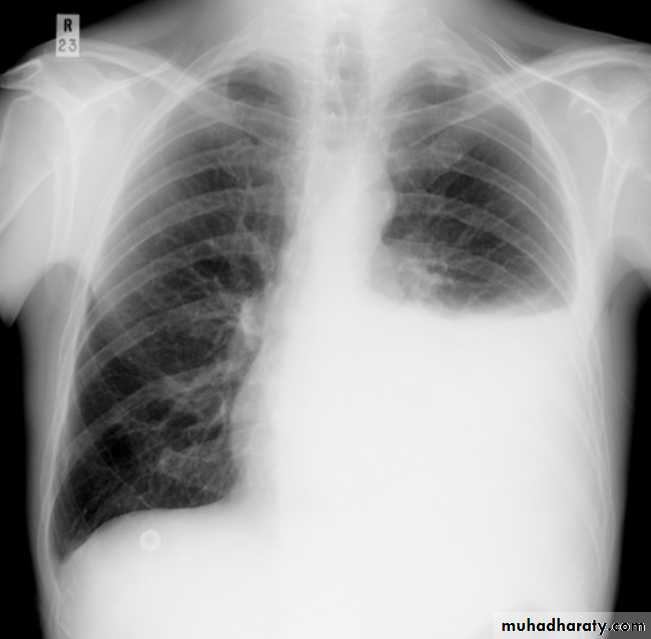

Pleural effusion

Pleural effusion tends to be used as a catch-all term denoting a collection of fluid within the pleural space. This can be further divided into exudates and transudates depending on the biochemical analysis of aspirated pleural fluid. Essentially it represents any pathological process which overwhelms the pleura's ability to reabsorb fluid.Radiographic appearances

Plain radiographChest radiographs are the most commonly used examination to assess for presence of a pleural effusion, however it should be noted that on a routine erect chest x-ray as much as 250-600 ml of fluid is required before it becomes evident 6. A lateral decubitus film is most sensitive, able to identify even a small amount of fluid. At the other extreme, supine films can mask large quantities of fluid.

CXR (erect)

Both PA and AP erect films are insensitive to small amounts of fluid. Features include:

blunting of the costophrenic angle

blunting of the cardiophrenic angle

fluid within the horizontal or oblique fissures

eventually a meniscus will be seen, on frontal films seen laterally and gently sloping medially (note: